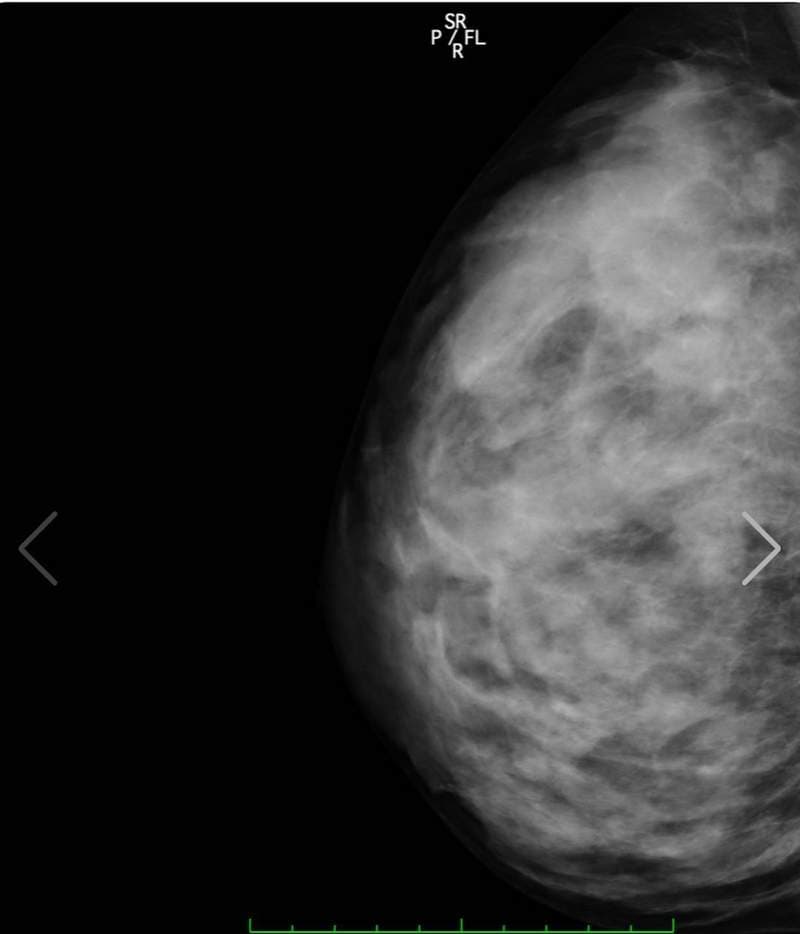

至于今天开头跟大家分享的上空X光照,大家千万不要觉得阿漆又要唬烂骗点阅,实际上她在最近真的有公开自己的X光照片,其实她在之前8月的时候曾确诊新冠肺炎,休养一个月之后康复已经完全健康,现在做个体检也是确认不要有后遗症

另外之前有网友曾质疑她胸部作假,这么大肯定不是天然的胸部,而这次在社群媒体上公开自己的体检结果,也间接打脸掉这个说法,她的胸部没有任何填充物,而右胸上小小的黑点是胃泡,所以整体检查结果下来是很OK的